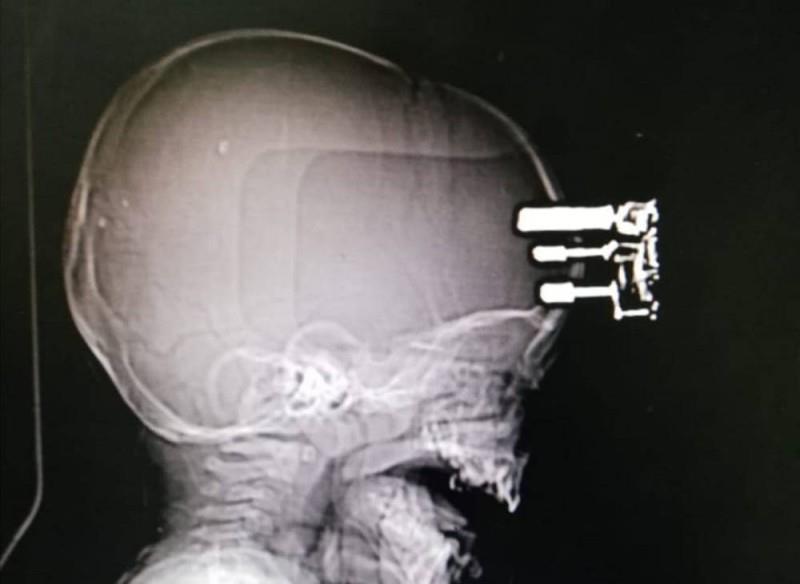

وتم إسعاف الرضيع فورا إلى المستشفى، حيث قام فريق طبي بفحصه وإجراء الأشعة اللازمة، حيث تبين أن الشاحن اخترق عظم الجمجمة وثبت فيها، فتم تجهيزه وإجراء عملية جراحية عاجلة له.

وتمت العملية بنجاح، حيث تم استخراج الشاحن من رأس الرضيع، وإصلاح تلف أغشية الدماغ وعلاج كسر الجمجمة، واستعاد الرضيع كامل وعيه، دون حدوث أي قصور حركي أو مضاعفات.